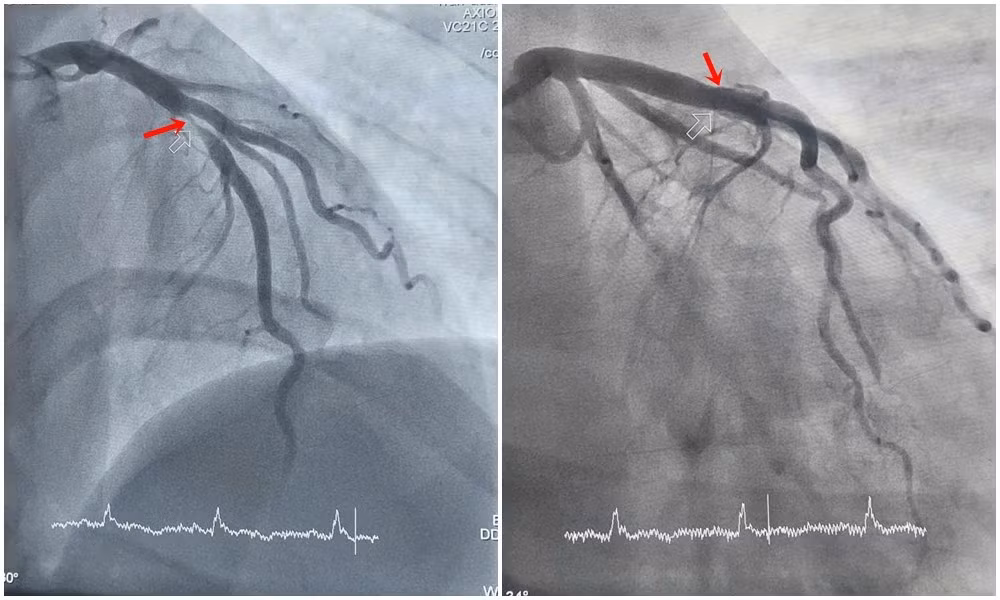

Bệnh nhân nhanh chóng được chuyển phòng can thiệp chụp mạch vành kiểm tra. Kết quả chụp cho thấy động mạch liên thất trước - một trong những nhánh mạch vành quan trọng nuôi dưỡng cơ tim, bị tổn thương nặng, hẹp khít 99%. Trước tình trạng nguy hiểm, các bác sĩ khoa Phẫu thuật và Can thiệp Tim mạch thực hiện can thiệp đặt stent nhằm tái thông máu nuôi tim, giúp người bệnh thoát khỏi tình trạng nguy hiểm.

Hình ảnh hẹp tắc động mạch liên thất trước của bệnh nhân H. được can thiệp tái thông. Ảnh BV